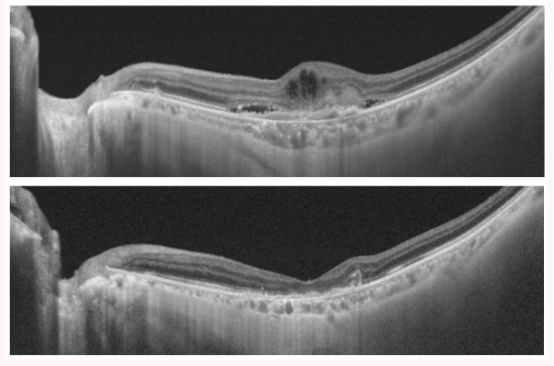

使用抗血管内皮生长因子(VEGF)剂治疗湿性老年性黄斑变性

在治疗前通过光学相干断层扫描(OCT)观察到的视网膜水肿(上图)在治疗后消失(下图)